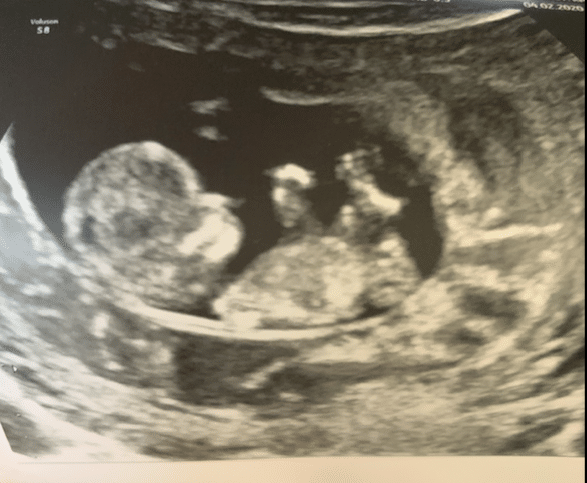

And that brings me here. I’ve had weekly ultrasounds both in Florida and Toronto, and everything has shown baby is measuring perfectly. I just did the early genetic screening so I’m awaiting those results, and then next after that will be the anatomy scan. Obviously I’ll be nervous until this kid is out but my mama gut is telling me this ones for keeps. I’ve been pretty nauseous this pregnancy and really crazy tired. But I just got to ween off my prednisone, estrogen and progesterone, so I am feeling so much better.